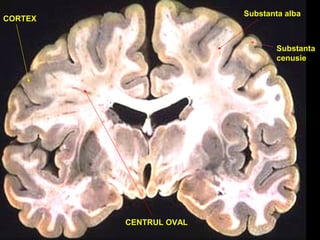

CORTEX

CENTRUL OVAL

Substanta alba

Substanta

cenusie